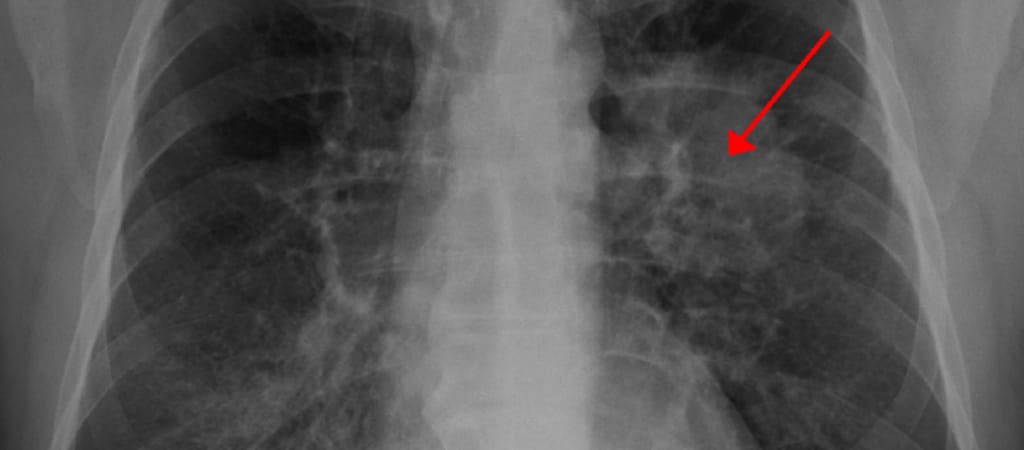

Horváth Péter programtervező matematikus, bioinformatikus kutatócsoportja komplex sejtbiológiai problémák, többek között az agykutatás és a daganatok személyre szabott gyógyászatának analízisét végzi a Lendület program támogatásával. A cél a daganatos betegségek és az agy kommunikációjának pontosabb, egysejt-szintű megértése mesterséges intelligencia segítségével. Az MTA Szegedi Biológiai Kutatóközpontban megalakuló csoport mögött az a felismerés áll, hogy a rendszer-biológiában különböző határtudományok szoros együttműködésére van szükség. A csoport új képfeldolgozási eljárásokat kombinál mikroszkópos képalkotó eljárásokkal, a mesterséges intelligenciában alkalmazott módszerekkel és egysejt-analitikai technikákkal. Olyan rendszer létrehozásán dolgoznak, amely automatikusan és a lehető leghatékonyabban képes biológiai minták feltérképezésére, majd egy szakember által értelmezhető leírására.